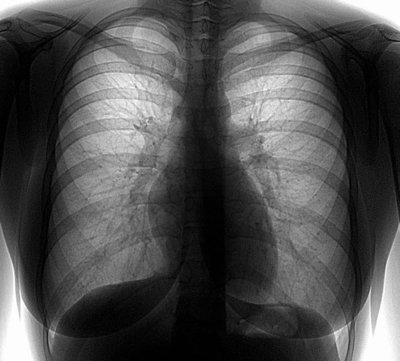

В рамках проведения мероприятий, приуроченных к Всемирному дню борьбы с туберкулёзом, в период с 21 по 27 марта 2015 г. (с 8.00 до 14.00) на площади Общественно-культурного центра г. Благовещенска, расположенного по адресу: ул. Ленина, 100, всем желающим будет проводиться флюорографическое обследование на передвижной флюорографической станции. Желающим пройти обследование при себе необходимо иметь паспорт. Напоминаем, что флюорография помогает своевременно выявить заболевание туберкулёзом и позволяет начать лечение болезни на самых ранних ее этапах. Согласно требованиям СП 3.1.2.3114-13 «Профилактика туберкулеза» в связи с достаточно высоким уровнем заболеваемости туберкулёзом среди населения Амурской области флюорографическое обследование должно проводиться всем лицам старше 15 лет не реже 1 раза в год. Уважаемые амурчане! Управление Роспотребнадзора по Амурской области призывает вас проявить активность в проведении данного мероприятия, направленного на защиту вашего здоровья и здоровья ваших родных и близких. |